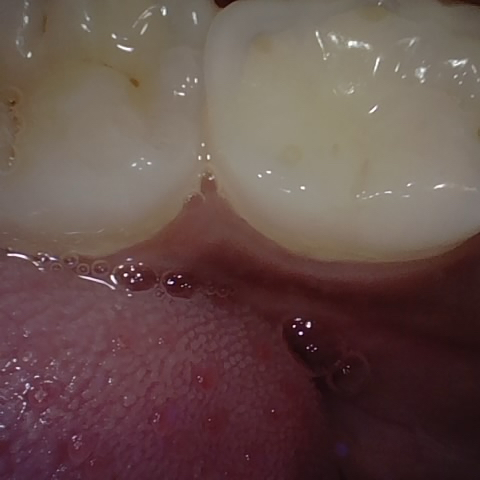

NHD25470

Annotated as "Good"